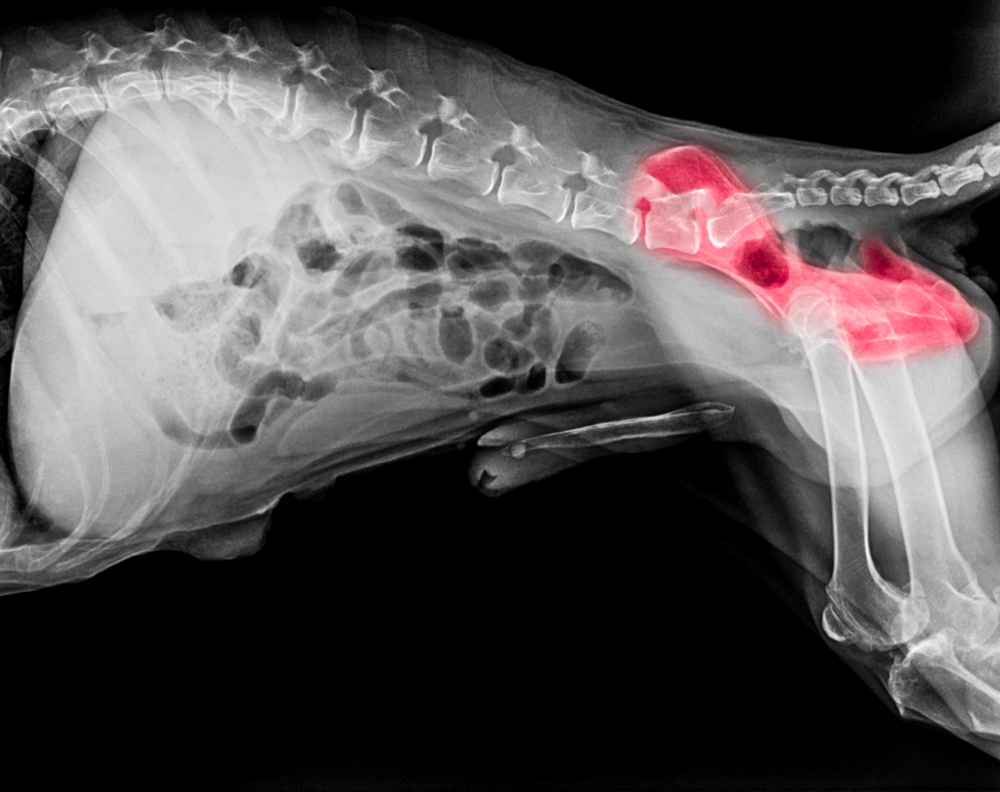

We can x-ray your dog’s hips for hip dysplasia at 2 years of age. We will forward these radiographs to the OFA, where board-certified radiologists will evaluate and grade your dog’s hips for OFA certification. Correct positioning of your dog is essential for proper radiographic evaluation, so a general anesthetic is required to make the procedure less stressful for him or her.